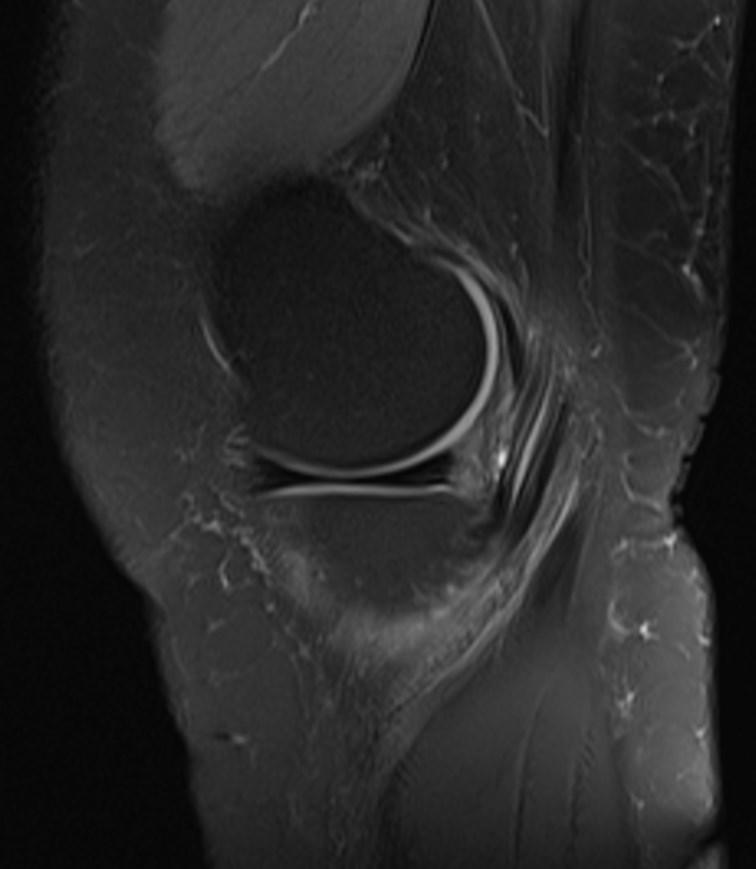

*32-year-old female present with pain along the proximal medial tibia.

What is the most likely diagnosis?

Answer: Pes anserinus bursitis

MR images showed edema-inflammation of the pes anserinus bursa which is located at the medial aspect of the knee deep to the pes anserinus tendons.

Pes anserinus bursitis refers to symptomatic inflammation of the pes anserinus bursa which is located at the medial aspect of the knee deep to the pes anserinus tendons.